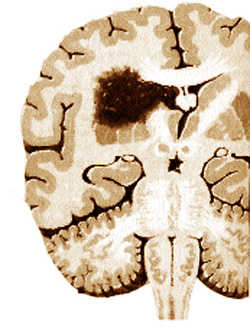

Le mécanisme de la migraine

Sont connus trois stades du trouble vasomoteur:

1. Tout commence par un spasme artériel (photo 1) qui réduit le débit sanguin à une partie du cerveau. A ce moment le patient voit flou, effacé, il perçoit dans le champ visuel des taches noires ou des points lumineux (corps flottants), mais la douleur n’a pas encore paru. On enregistre une libération de catécholamines (hormones du stress) de la glande surrénale.

2. Puis, rapidement, cette artère qui a été soumise à la vasoconstriction se dilate et le flux sanguin augmente, entraînant une vraie congestion locale – une phase de vasodilatation (photo 2). Maintenant vient la douleur, sourde ou pulsatile (comme les coups de marteau). S’il y a aussi des symptômes digestifs (nausées ou vomissements), ils sont la conséquence de l’irritation d’un certain centre corticale et ne sont pas liés à un trouble digestif.

3. Ensuite, la phase finale de l’œdème (photo 3) où se produit une inhibition des parois des artères du cuir chevelu et une infiltration œdémateuse cérébrale (diffusion du sang à travers les parois des vaisseaux sanguins dans le tissu nerveux), ce qui

explique la somnolence, l’apathie et de fatigue vers la fin de crise de migraine.